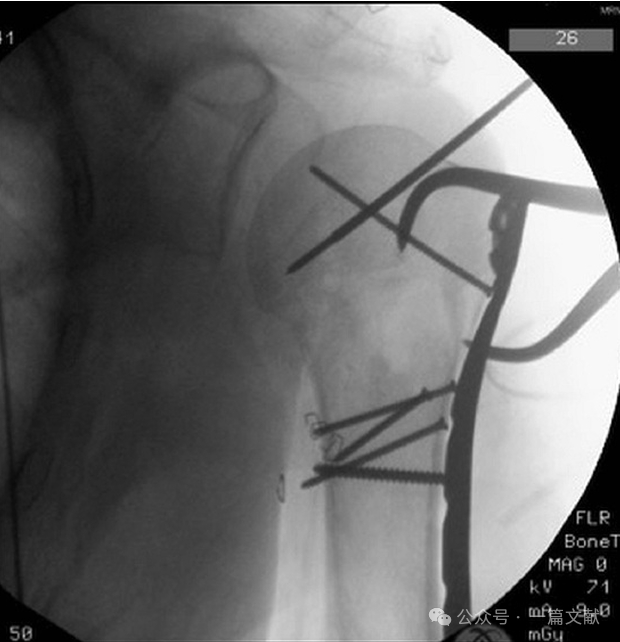

四,腋位片:

肩关节外展30-90°拍摄,此位片一般用于骨折复位且内固定以后,来评估术中复位以及内固定位置。主要可以观察:盂肱关节匹配情况,大、小结节复位情况,肱骨近端矢状面的对位情况,肱骨头后倾角,钢板位置以及螺钉长度。如下图:

体位与拍摄角度: